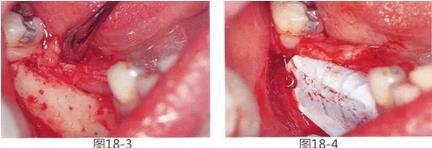

360截圖20170422142114811.jpg

圖18-3  將粘膜剝離,露出牙槽嵴的狀態(tài)。可以看到牙槽嵴非常薄。為了促進(jìn)牙槽嵴出血,在皮質(zhì)骨上進(jìn)行穿孔。

圖18-4  進(jìn)行骨移植后,使用釘子將Gore-Tex鈦強(qiáng)化膜固定。